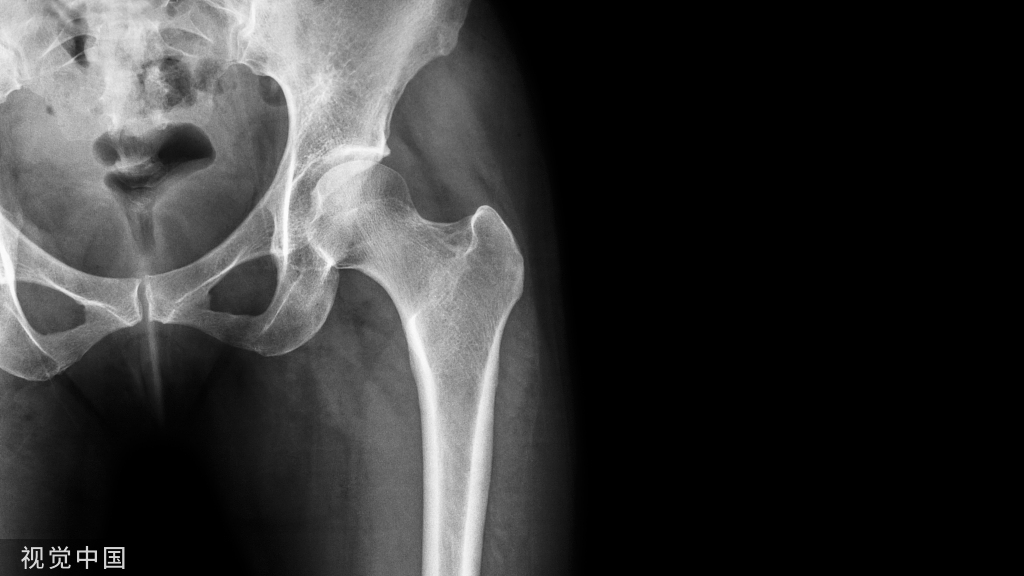

25岁时她回到诊所复查,当时她没有任何症状,否认存在背痛、腹痛、麻木、无力或步态障碍。检查时,她双侧上肢和下肢的力量和感觉完全正常。下肢血管检查显示双侧足背肌和胫后脉搏正常。站立的全脊柱X光片显示内固定无松动断裂或近端交界区后凸畸形。可观察到残余的胸腰段脊柱侧弯伴有凸起的右侧胸廓曲线和代偿性左下骨盆倾斜(图 1)。CT扫描可观察到右侧T12椎弓根螺钉尖端超出T12椎体皮质前缘5mm,进入右后外侧主动脉壁,没有血肿或假性动脉瘤的证据(图 2 )。尽管主动脉内的椎弓根螺钉尖端在临床上仍无症状,且在影像学上没有进展,但患者和她的家人选择继续进行手术干预以防止将来可能出现的并发症。

图1 修复手术前获得的前后位(左)和侧位(右)脊柱侧弯X光片。